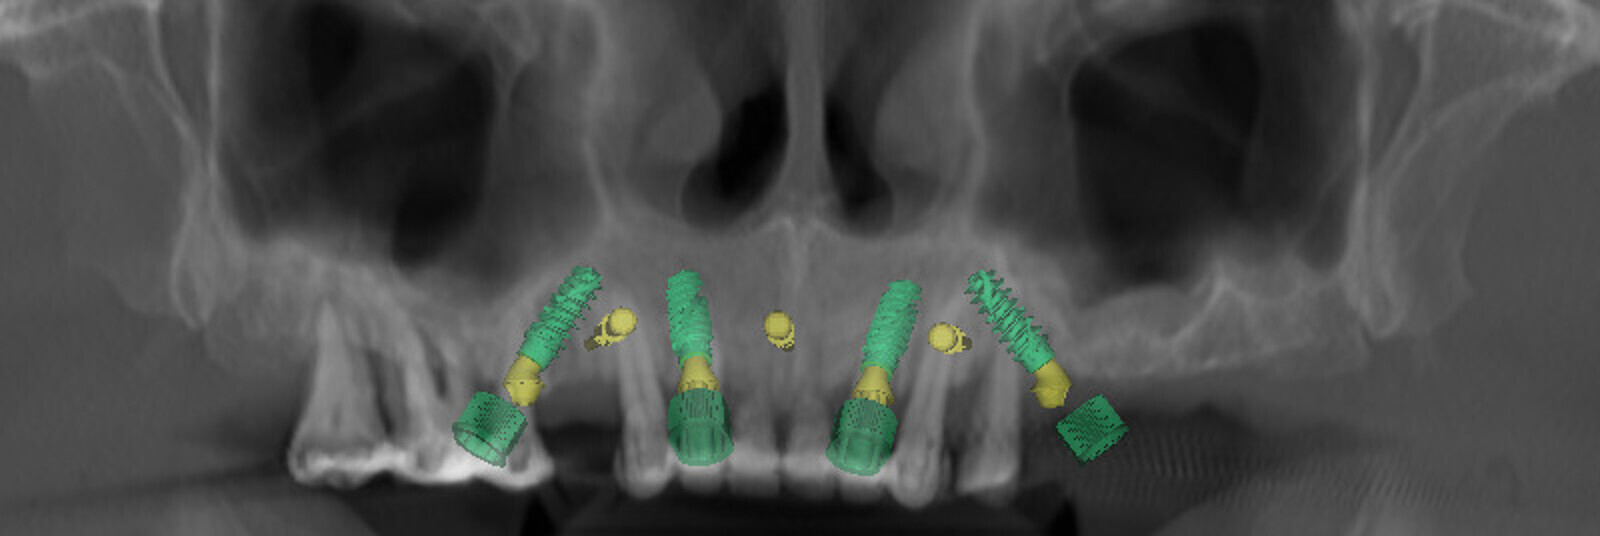

Compromised maxillary dentition treated with Straumann Pro Arch and a digital workflow